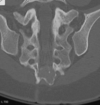

Masculino, 12 anos

Síndrome da sincondrose isquiopúbica assimétrica (Doença de Van Neck-Odelberg)

Variante da normalidade (em geral assintomático)

Crianças

Alargamento e radioluscência na sincondrose isquiopúbica, que simula neoplasias, infecção;